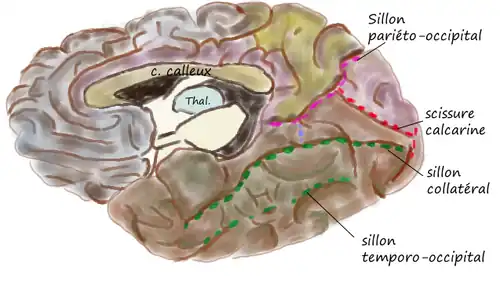

Le sillon calcarin commence près du pôle occipital par deux rameaux convergents et court vers le haut et vers l'avant jusqu'à un point situé légèrement au-dessous du splénium du corps calleux, où il est rejoint et interrompu à angle aigu par la partie médiale de la scissure pariéto-occipitale. La partie antérieure de la scissure calcarine donne naissance au renflement du calcar avis dans la corne postérieure du ventricule latéral.

Le cortex visuel primaire est enfoui à l'intérieur de la scissure calcarine, sur ses berges supérieures et inférieures. Les berges supérieures reçoivent les informations des quadrants inférieurs du champ visuel et inversement, les berges inférieures celles des quadrants supérieurs.

La vision centrale est située à la partie postérieure de la scissure calcarine et la vision périphérique à la partie antérieure. La quantité de cortex dévolue au traitement de l'information visuelle n'est pas proportionnelle à la surface de champ visuel correspondant. Une zone de cortex significativement plus étendue qu'ailleurs traite les informations en provenance de la fovea[1]. Ce phénomène est connu sous le nom d'« agrandissement cortical ».

| Face interne | Vue inféro-interne du cortex, d'après une pièce anatomique |